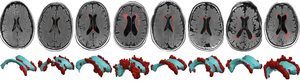

Johannes Weickenmeir at Stevens Institute of Technology (IMAGE)